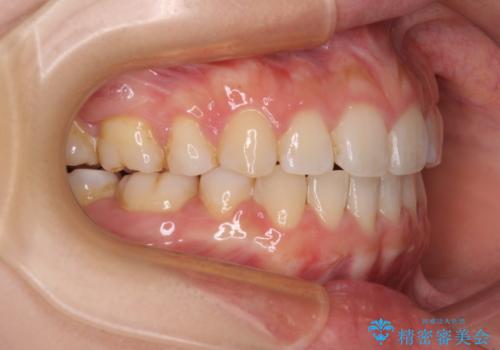

- 前歯が突出しているために口が閉じられないとのことで来院された患者様です。

上下ともに顎が小さく、歯列が前方に突き出していたため、上下左右の第一小臼歯4本を抜歯し、口元の突出感を改善していくこととしました。

口元の突出感が改善されると睡眠中の口呼吸が予防でき、鼻炎などの疾患予防に繋がると言われています。